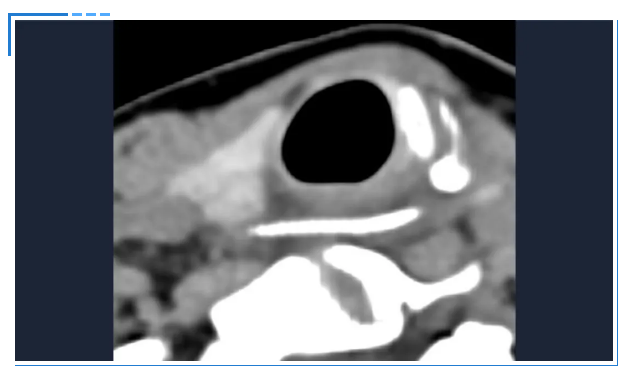

消化内镜室迅速启动取刺准备,当胃镜缓缓抵达食管入口时,清晰可见一根长约3cm的鱼刺,正斜斜嵌顿在食管入口的右侧壁,鱼刺尖端已刺入黏膜下层,周围黏膜因刺激出现明显充血水肿。更棘手的是,鱼刺恰好卡在食管入口的生理拐弯处,这个部位是食管与咽喉的衔接点,角度刁钻,内镜难以稳定固定位置。

操作医生首先尝试使用常规透明帽辅助取刺。透明帽顺利扩张开食管入口,将鱼刺完整暴露在视野中,但当异物钳从内镜操作通道伸出时,问题出现了:由于食管拐弯的角度限制,内镜操作通道与鱼刺的位置夹角过小,异物钳的活动空间被严重压缩。医生反复调整内镜角度和异物钳方向,要么视野被遮挡无法看清鱼刺,要么异物钳无法精准对准鱼刺主体,尝试了数次后,始终无法牢固夹持鱼刺,首次取刺宣告失败。